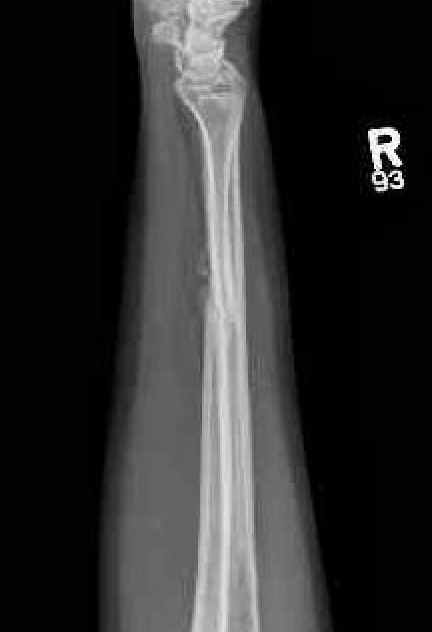

Night stick injury - direct blow or trauma to ulna

Distal 1/3

Midshaft / middle 1/3

Proximal - beware Monteggia / radial head dislocation